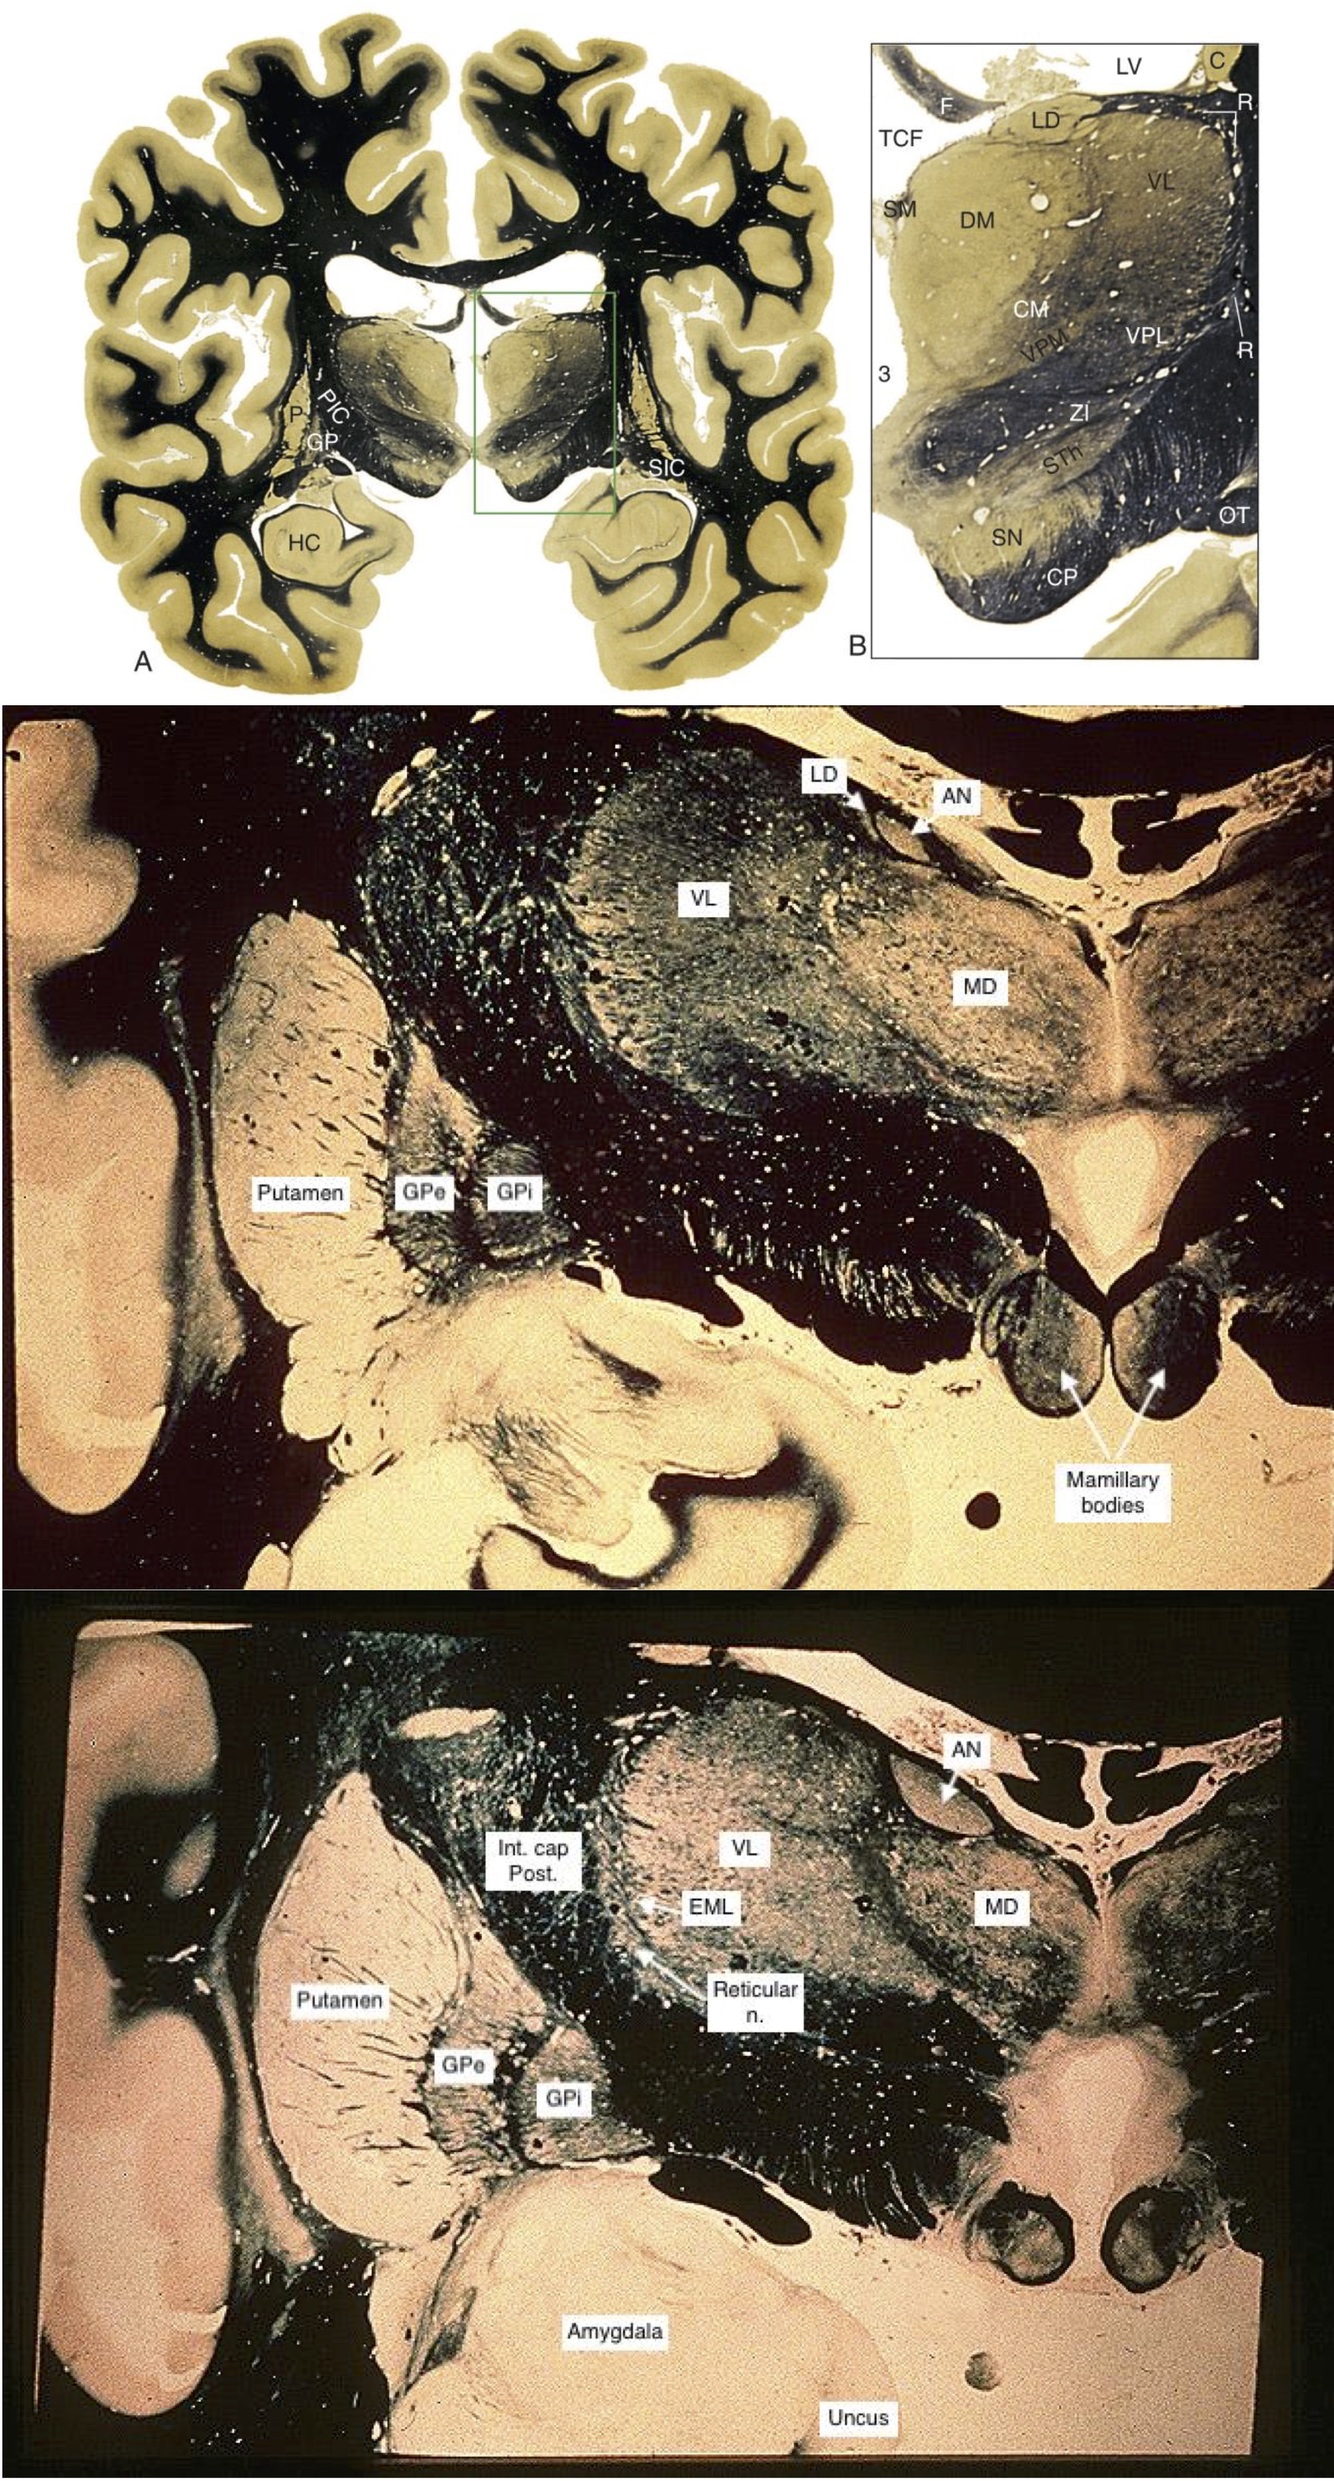

Mid-Thalamus